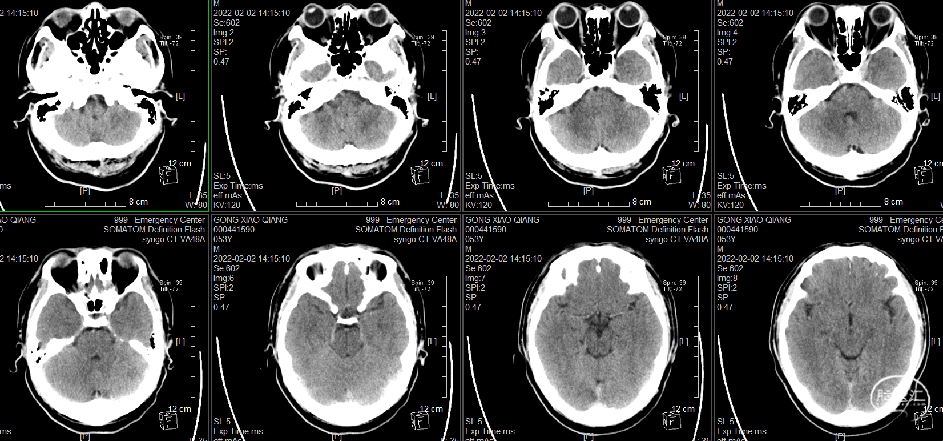

头颅CT(溶栓后复查)

头颅CT(溶栓后复查):右侧小脑梗塞可能,建议复查或MRI检查。